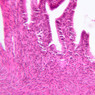

Corpus Luteum

After rupture of the Graafian follicle, the walls collapse and become folded. Thus, strands of tissue from the theca interna penetrate, to some extent, the mass of granulosa cells. Bleeding from the theca interna may form a blood clot in the antrum. The majority of the cells of the corpus luteum are derived from the granulosa cells. Both the granulosa cells and the cells of the theca interna enlarge and accumulate lipid, thus becoming lutein cells. There are two types of lutein cells - granulosa lutein cells that have a large, vesicular nucleus and vacuolate cytoplasm, and theca lutein cells that are distinguished by smaller darker nuclei. Corpus Luteum (slide B-54, human ovary, H&E [1x-labeled, 2.5x, 10x, 20x, 40x-labeled] [1x-labeled, 1x, 2.5x] [1x, 1x, 1x] 1x, 2.5x, 10x]; B-95, H&E [2.5x])